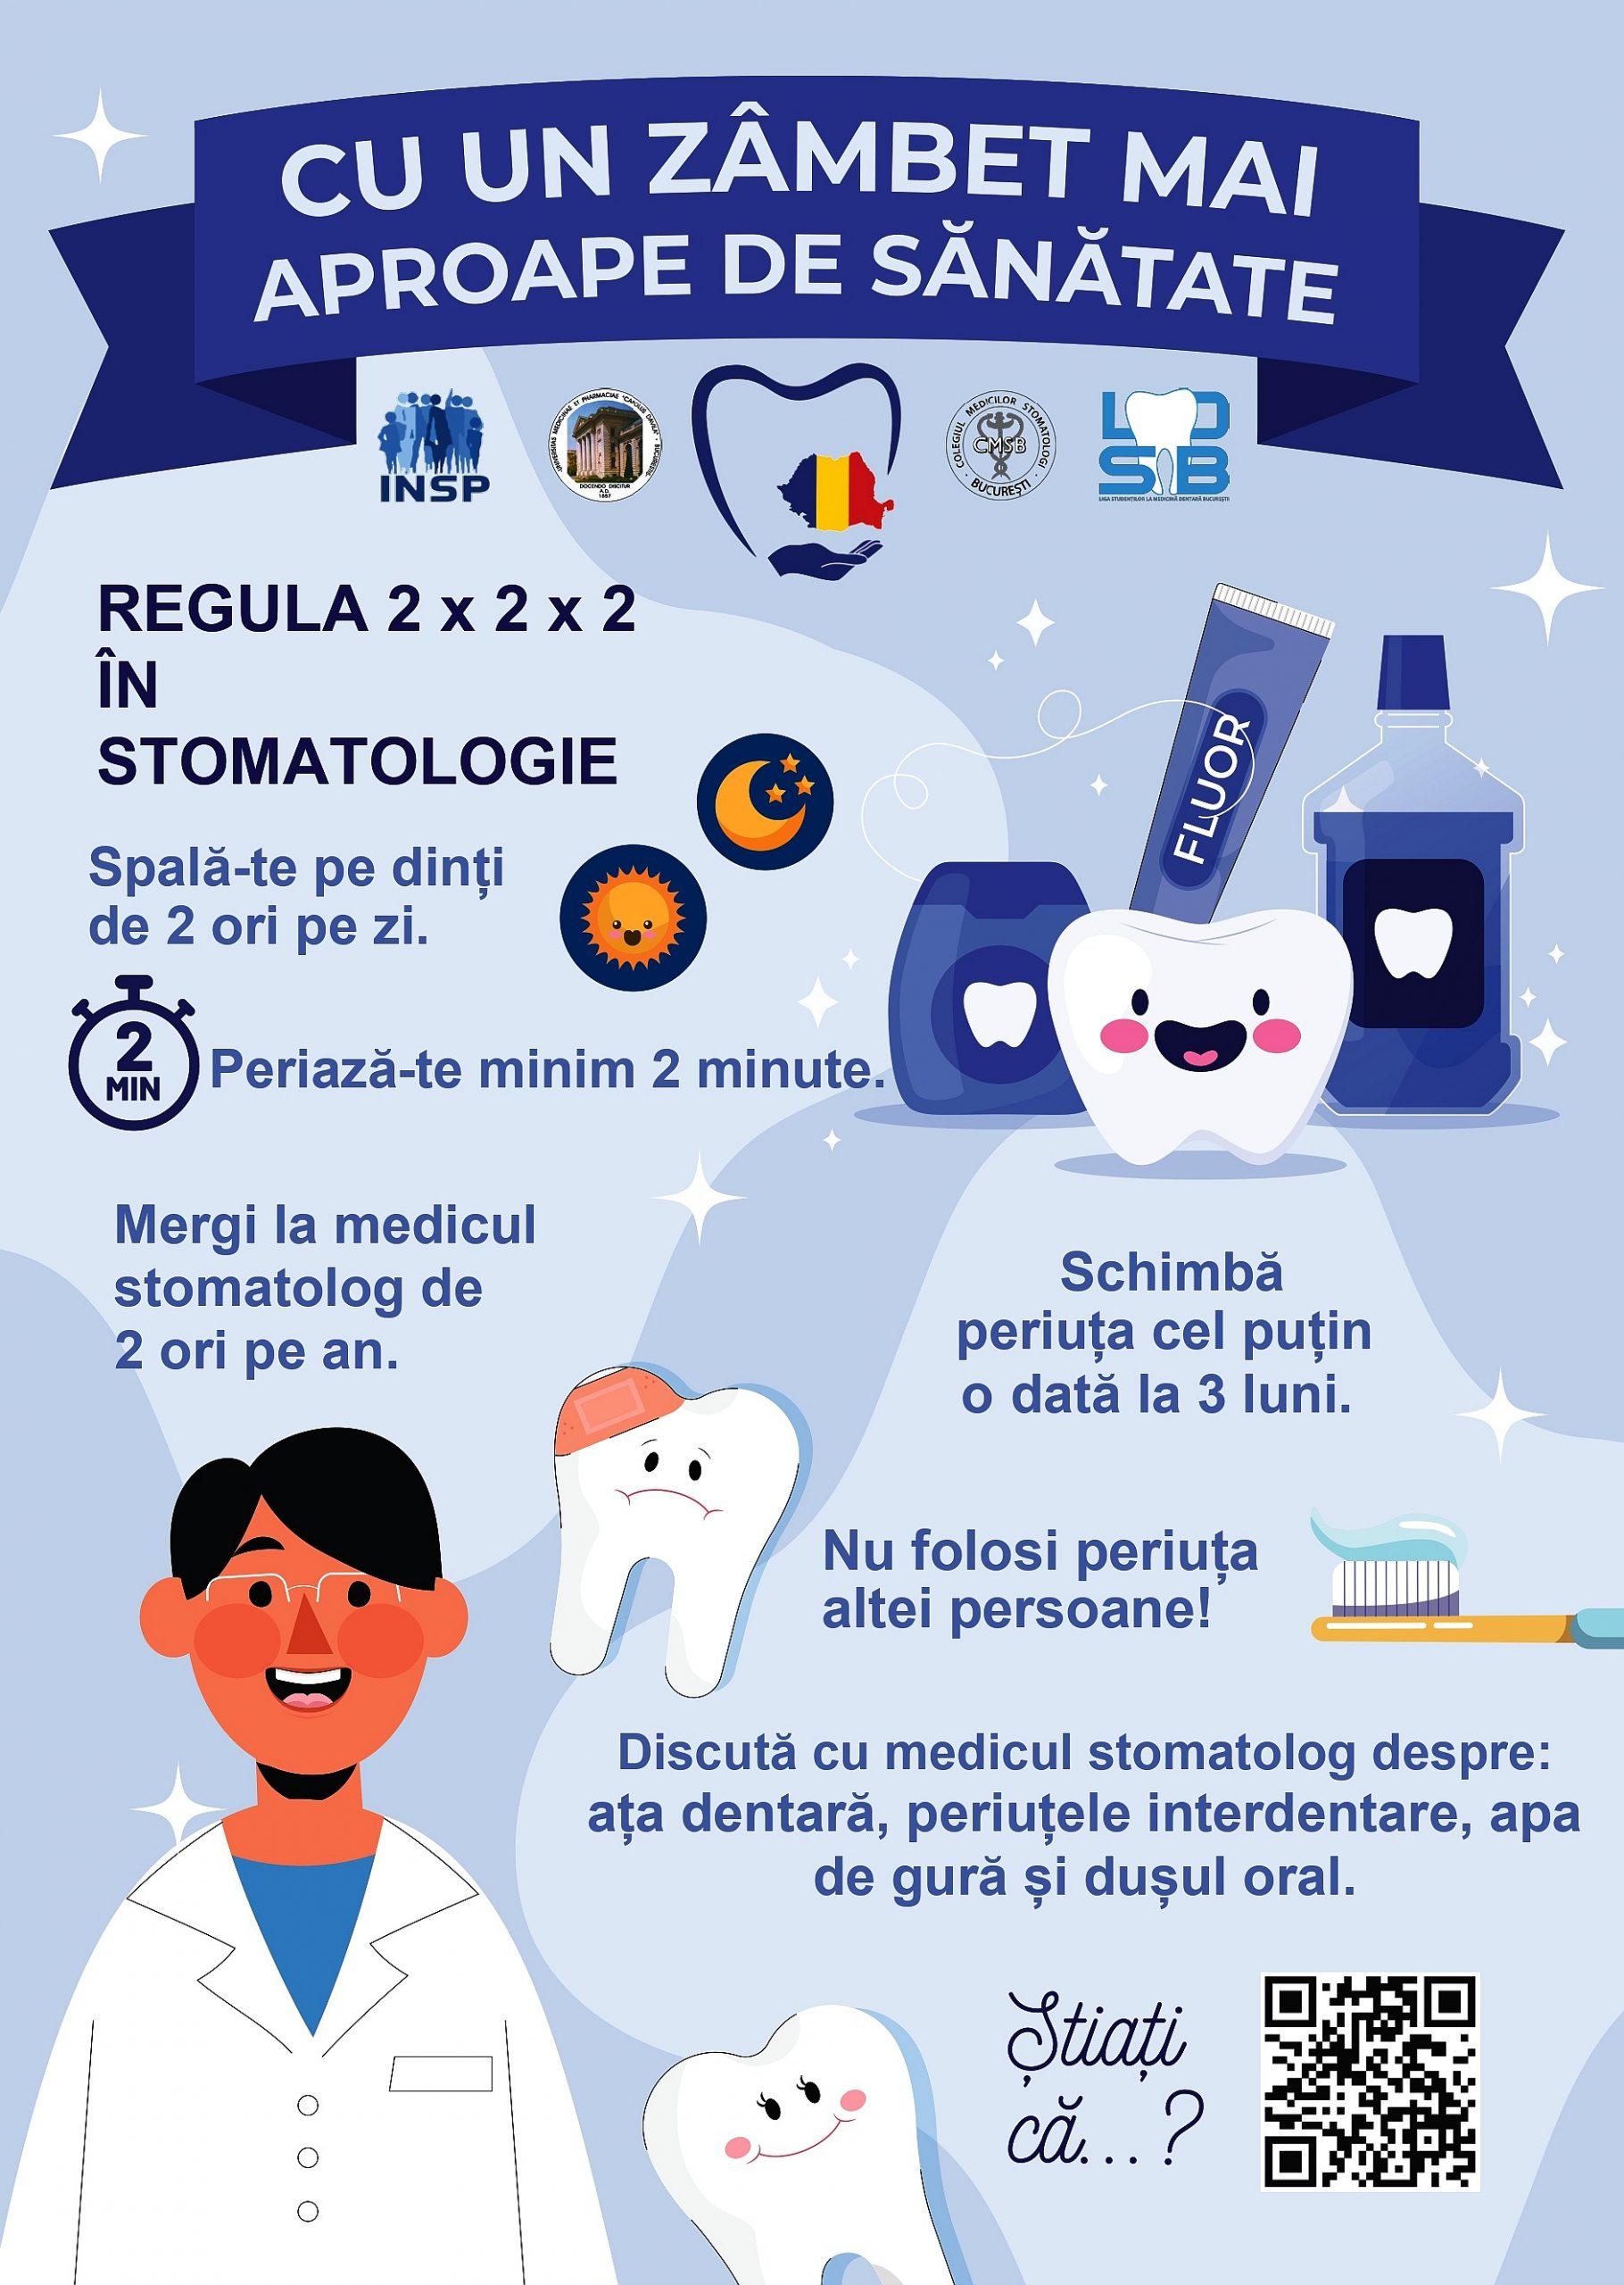

Menținerea unei rutine de îngrijire orală consecvente – inclusiv periaj corect, curățare interdentară și curățarea limbii – poate ajuta la reducerea acumulării plăcii bacteriene care contribuie la inflamația gingiilor. Modificări ale stilului de viață, precum renunțarea la fumat, un regim alimentar echilibrat cu limitarea alimentelor foarte fermentabile și hidratarea adecvată, pot susține sănătatea gingiilor și pot contribui la prevenție.

Vizitele regulate la medicul dentist pentru evaluări și igienizări profesionale, împreună cu gestionarea factorilor generali de sănătate – de exemplu controlul glicemiei sau revizuirea medicației care poate influența mucoasa orală – pot susține eforturile preventive. Dacă observați semne persistente de inflamație, discutați cu un specialist; pentru resurse suplimentare accesați: /?s=gingivita

R: Îmbunătățiți igiena orală prin periaj regulat cu o tehnică corectă, curățarea interdentară zilnică și folosirea unei ape de gură antiseptice recomandate de specialist. Evitați fumatul și mențineți controale stomatologice regulate pentru detartraj profesional. Dacă simptomele nu se ameliorează, consultați un medic dentist.